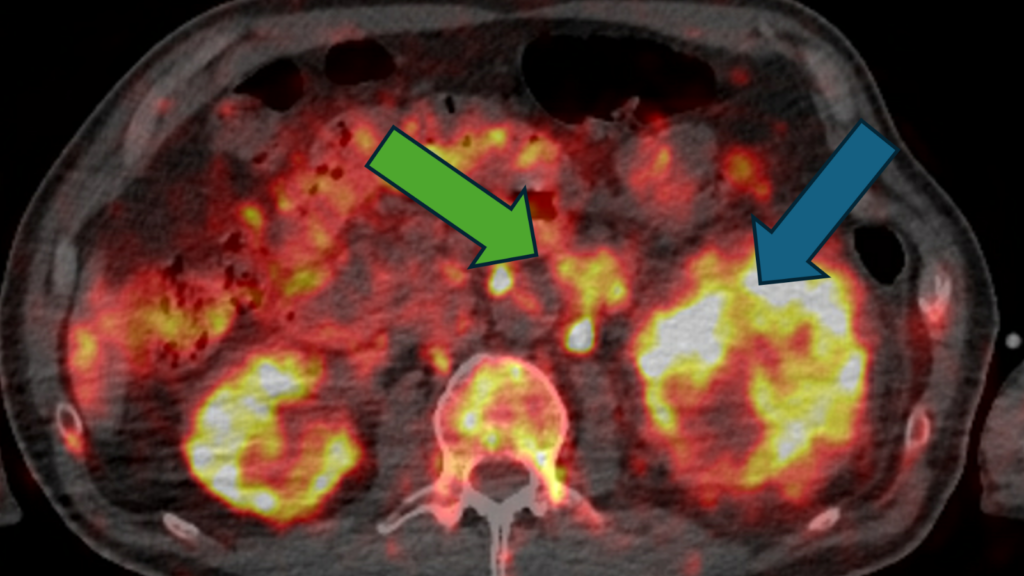

The trial, called iPREDICT, uses an investigational imaging agent called CD8 ImmunoPET which illuminates CD8+ cells on a PET scan.

CD8+ cells have been shown to attack and kill cancer cells and where they are located may indicate how well a patient responds to immunotherapy – a treatment which uses the immune system to find and attack cancer cells.

Currently, the only way to determine the number of CD8+ cells is by biopsy, but this only provides information on a single tumour lesion. CD8 ImmunoPET could provide important information on these cancer-killing cells in the body.